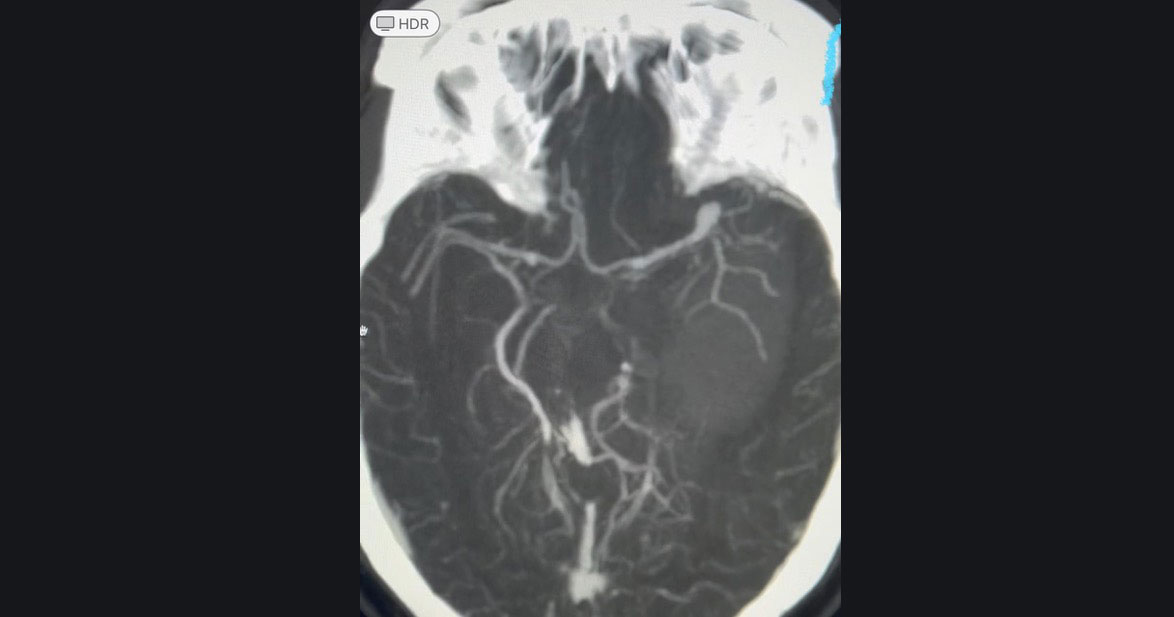

Arteriovenous Malformations (AVM)

An AVM is an abnormal tangle of blood vessels connecting arteries and veins, bypassing capillaries. This can lead to reduced oxygen supply to brain cells and cause symptoms like headaches, seizures, and neurological deficits. Treatment options include surgery, endovascular procedures, and radiosurgery. Dr. Yeole has expertise in both open surgery and radiosurgery for AVMs, which gives him more than one option to solve complicated disease entity like AVM.